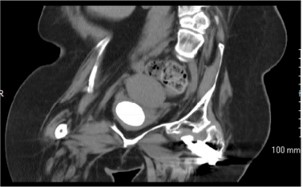

• Fallbericht über die Behandlung von harten, 4 cm großen, eiförmigen Blasensteinen mit einer Dichte von 1300 HU mit LithoClast® Trilogy

Wir stellen einen Fall von Zystolitholapaxie mit dem LithoClast® Trilogy Lithotripter-Gerät per Urethra über ein starres 26F Nephroskop bei einer 36-jährigen Frau mit Chondrodysplasie, Querschnittslähmung, Kontrakturen und Blasenvergrößerung in der Vorgeschichte vor, die mit einem sauberen intermittierenden Katheterismus behandelt wurde. Der Stein hatte einen Durchmesser von 4 cm mit durchschnittlich 1300 Hounsfield-Einheiten und bestand aus 45% Kalziumphosphat, 40% Struvit und 15% Ammoniumurat.